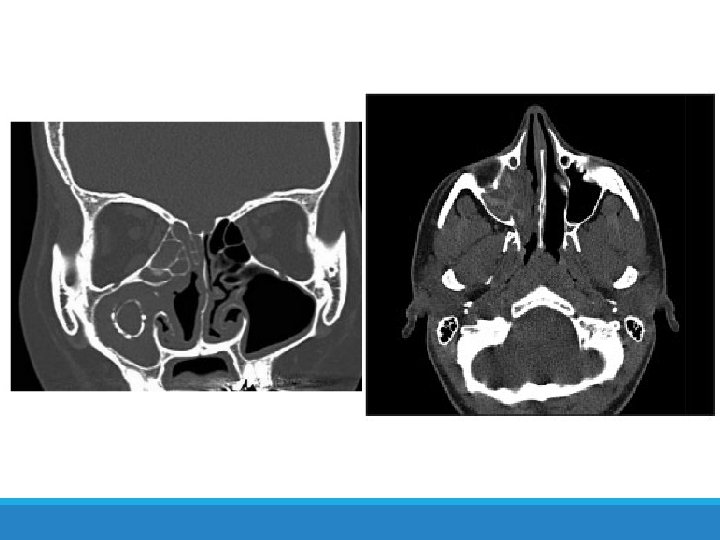

Case: Diagnosis Exacerbation after ingestion of aspirin or other non-NSAIDs Starts with intractable nasal congestion and watery rhinorrhea Refractory to pharmacologic Treatment Progressive, may become associated with anosmia Specific Ig. E tests negative Nasal polyposis Total or near-total opacification of the sinus cavities (on CT) An individual with rapid onset of a severe attack with no previous insult who necessitates acute emergency care, intensive care unit admission, or endotracheal intubation